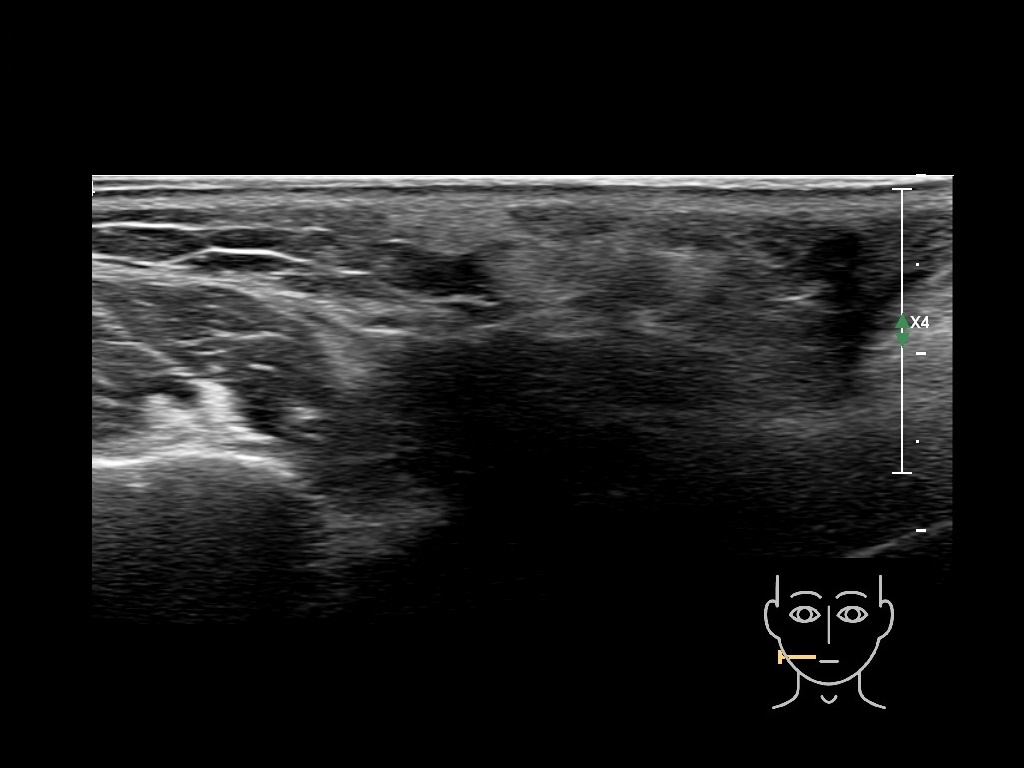

Draw in the image on the right where the fillers are located. To check if your answer is correct, please click on the secondary image.

Draw in the second image below where the fillers are located. To check if your answer is correct, swipe the first image to the right.